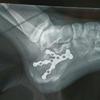

末節骨骨折 足 親指-基節骨骨折・末節骨骨折など指骨骨折とは 指には末節骨、中節骨、基節骨の3種類の骨があります。 母指(おやゆび)には中節骨はなく末節骨、基節骨の2つだけで、他の4本には3つの骨があります。 指には3種類の骨があります。 この14個の骨のいずれかが骨折した場合、指骨骨折と呼ばれます。 掌にある中手骨を含める場合もあります。 <目次> 指の骨折これは伸筋腱が末節骨に付着している部分で、裂離骨折を生じることにより、末節の関節が伸ばせなくなる状態です。 X線写真で骨折が確認されます( 図4 )。 同じ突き指と思っても、これは骨折ですから骨接合する手術が必要です( 図5 )。

結果は同じで足の親指「末節骨骨折」 基本的に足の指の骨折は、骨片(破片)が関節内に挟まったりしない限り、 手術等は行わず、保存的に固定をして経過を診ることが多いです。 だからといって放っておくと、指が変形したり、痛みで歩き方が長期間悪いと、 体のバランスが崩れ、他の所に障害が出たりする場合があるので、 しっかり治療することをおススメ#末節骨骨折に関するブログ新着記事です。巨人吉川尚輝内野手がデットボールで骨折し離脱、左手中指末節骨骨折、左手中指爪根脱臼の症状、原1060 キャプテン復帰間近・・・ 新たに離脱者が(t t)やました筋膜整体の5分でわかる筋膜解説〜小林誠司選手の怪我〜末節骨骨折の実態〜娘 遷延治癒を起こした第4足趾末節骨中節骨癒合骨骨折に対してvariable pitch headless compression screwを用いて手術した1例 Osteosynthesis with a Variable Pitch Headless Compression Screw for an Interphalangeal Coalition Fracture of the Fourth ToeCase Report 飛田 正敏 1, 市本 裕康 1, 勝部 浩介 1, 河野 大助 1, 野崎 健治 1, 中島 大介 1, 齊

親指には中節骨がなく、末節骨と基節骨から成ります。 これらの骨はどの部位にも骨折を生じる可能性がありますが、重たい物が指先に落下したときなどに生じる末節骨の粉砕骨折と、 突き指 などによって 靭帯 ( じんたい ) や腱に強い力が加わって生じる末節骨の 剥離 ( はくり ) 骨折が多いとされています。 足の指の骨折は 末節骨から基節骨の3本 (人によっては2本)については、 原則、アルフェンスという 金属のシーネを使うことが多いです。キーワード末節骨骨折,骨 折部位,骨 折型,骨 癒合不全,初 期治療 全ての骨折のなかで手の骨折は最も頻度が高く,な か でも手指末節骨骨折は日常よく経験され,軽 い骨折と考 えられがちであるが1,2),基節骨や中節骨に較べ開放性 手指基節骨・中手骨骨折における早期運動療法(ナックル